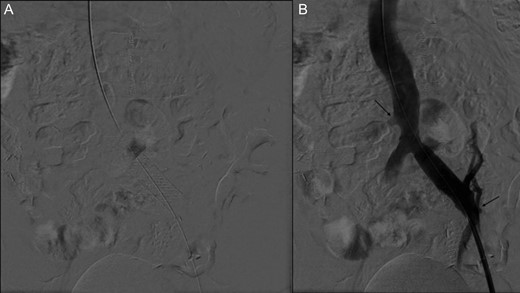

Initial angiography demonstrating thrombus in left common iliac vein with surrounding collaterals.

Two months after her transplant she developed abdominal pain and a CT scan was performed. Imaging demonstrated an extensive thrombus in the left common and external iliac veins, with compression of the left common iliac vein superior to the thrombus (Fig. 2). An interventional cardiology team performed angiography which showed a 100% occlusive lesion in the left CIV, with thrombotic defect in the left EIV, and patent pancreatic SMV and left renal vein. Balloon angioplasty and combined Angiojet and manual thrombectomy of the left common and external iliac veins was performed. A 16 mm x 40 mm Wallstent self-expanding metal stent was deployed in the left CIV, with a proximal landing site in the IVC, just distal to the pancreatic vein graft. Post-procedure angiography demonstrated a 30% residual stenosis, with patent flow through the LCIV and LEIV, and both the pancreatic and renal grafts. She was started on therapeutic anticoagulation after the procedure. Surveillance imaging 6-months post-procedure demonstrated no residual clot burden and appropriate stent positioning. Labs at 1 year follow up show persevered allograft function, with creatinine 0.91, amylase 88 and lipase 140, and no insulin requirements.